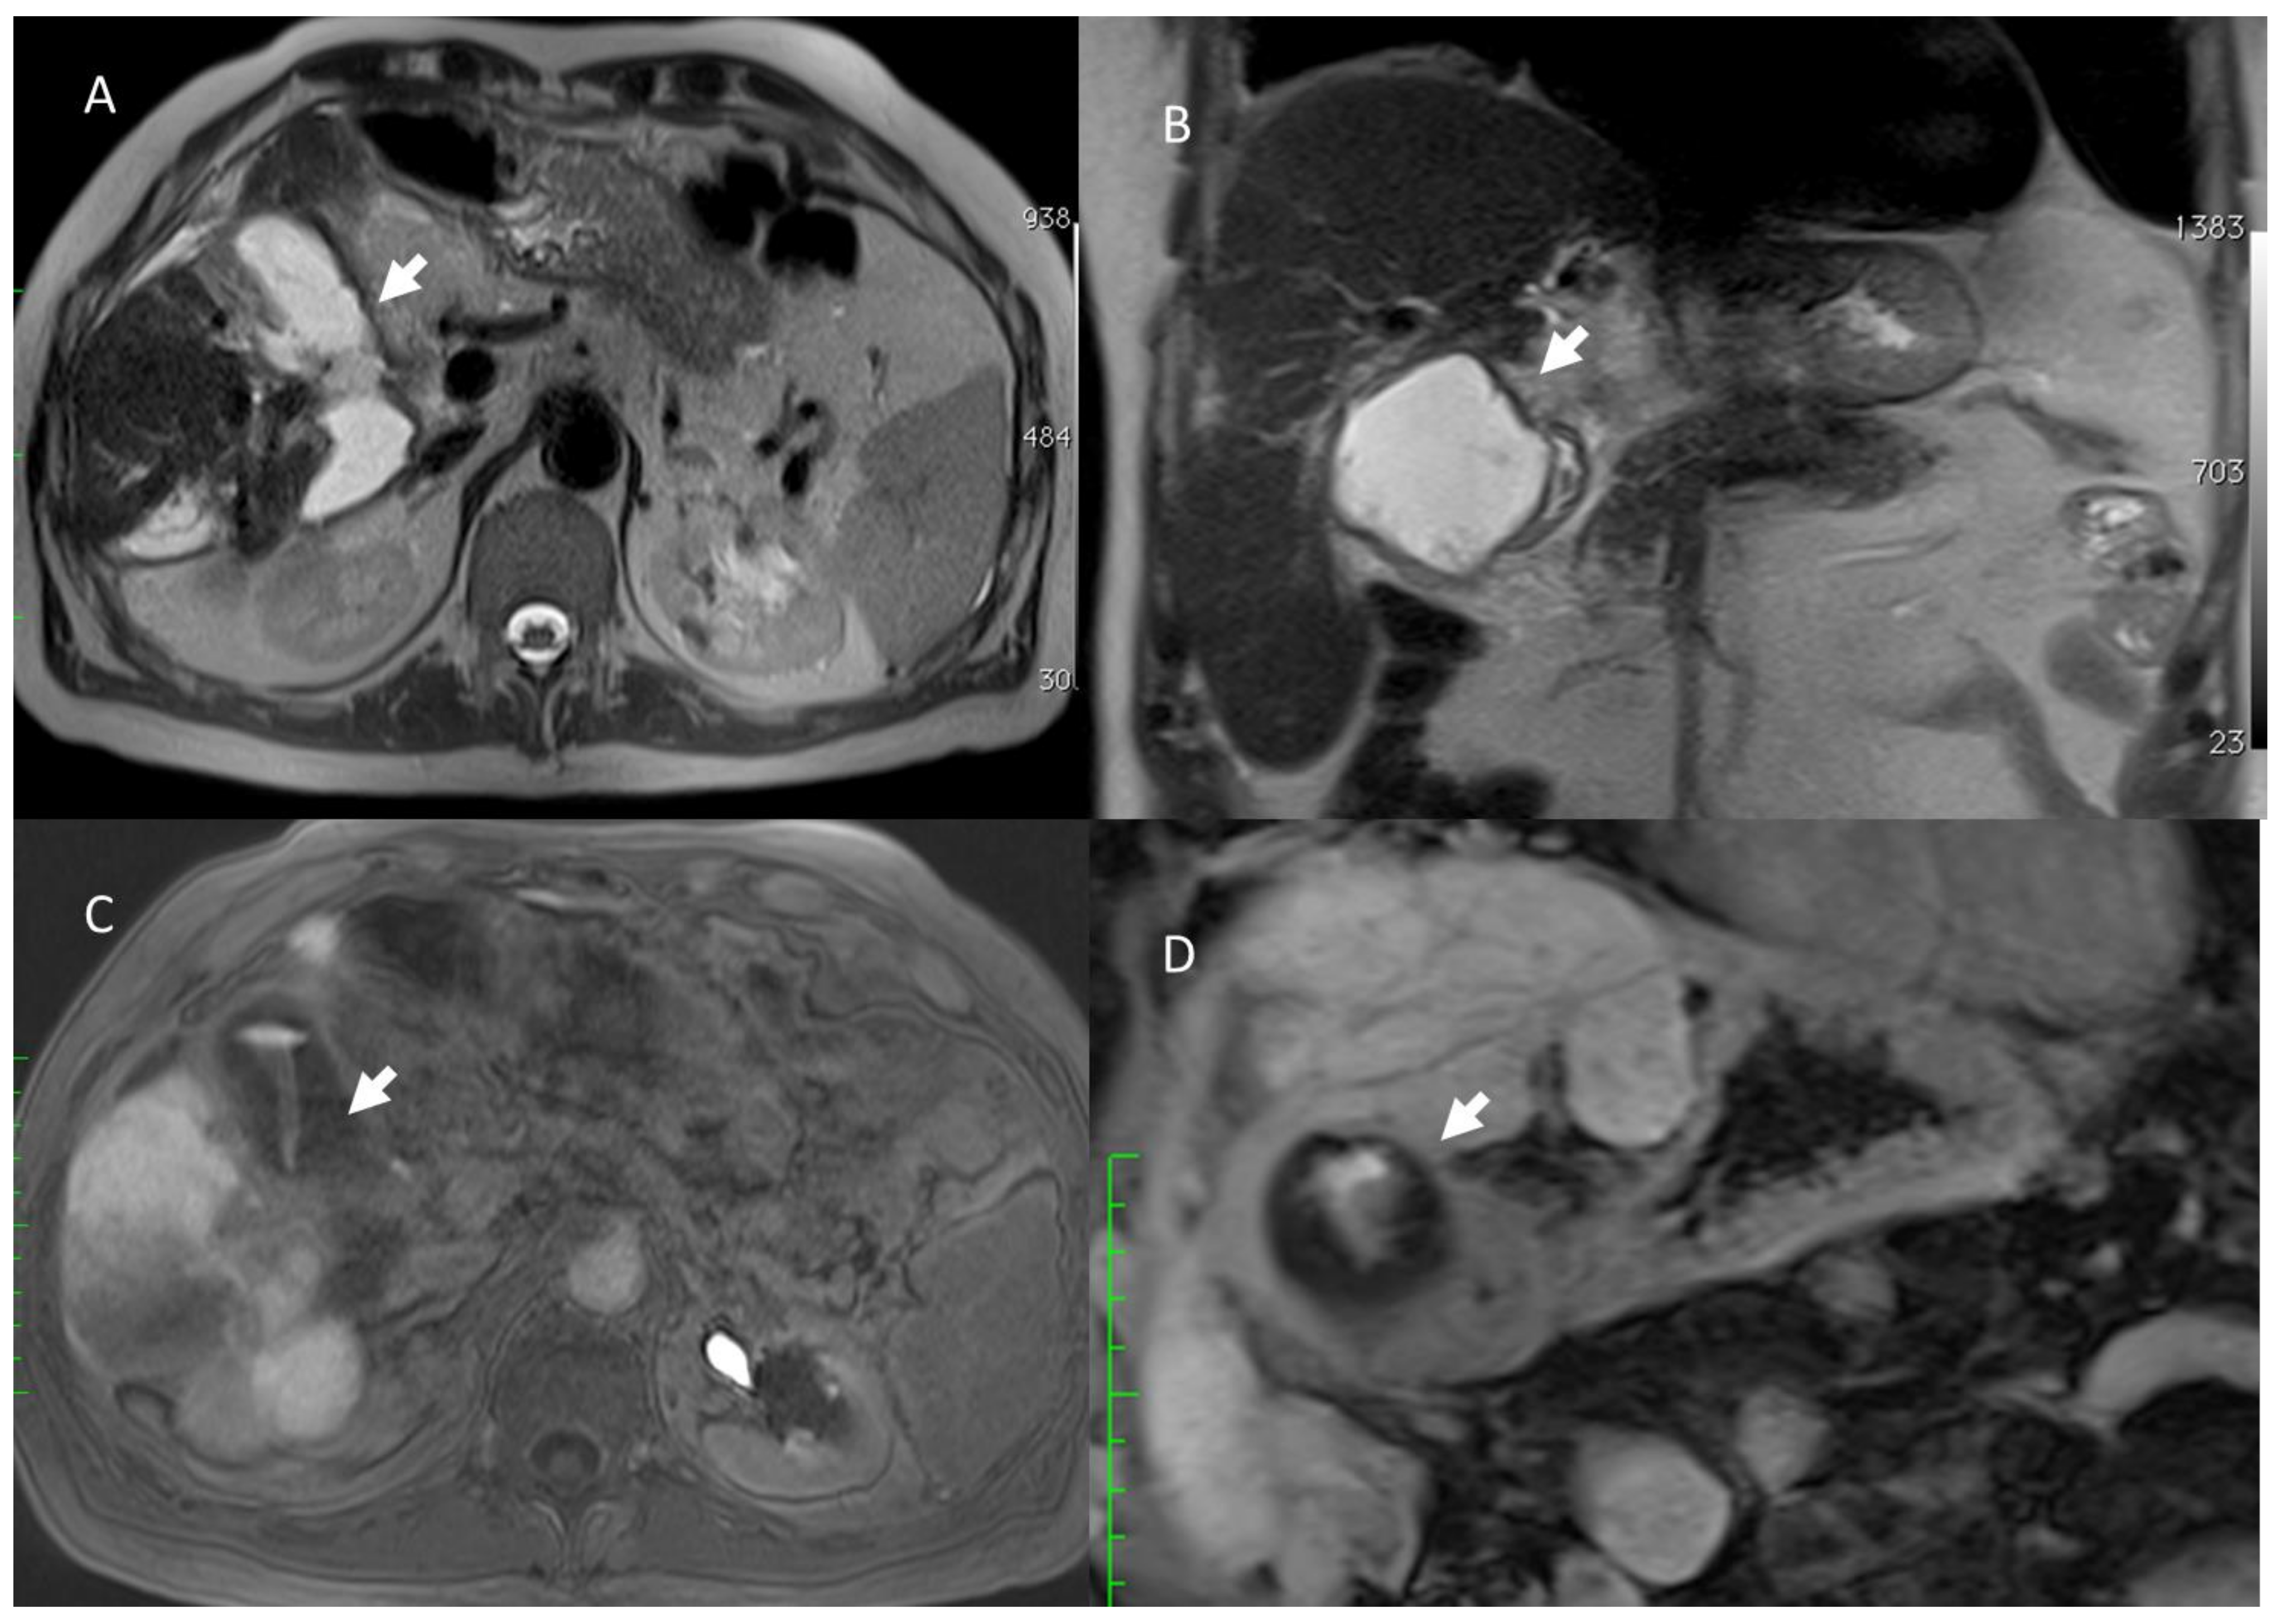

- Granata, V.; Fusco, R.; Catalano, O.; Piccirillo, M.; De Bellis, M.; Izzo, F.; Petrillo, A. Percutaneous Ablation Therapy of Hepatocellular Carcinoma with Irreversible Electroporation: MRI Findings. Am. J. Roentgenol. 2015, 204, 1000–1007. [Google Scholar] [CrossRef] [PubMed]

- Granata, V.; Fusco, R.; Salati, S.; Petrillo, A.; Di Bernardo, E.; Grassi, R.; Palaia, R.; Danti, G.; La Porta, M.; Cadossi, M.; et al. A Systematic Review about Imaging and Histopathological Findings for Detecting and Evaluating Electroporation Based Treatments Response. Int. J. Environ. Res. Public Health 2021, 18, 5592. [Google Scholar] [CrossRef] [PubMed]

- Granata, V.; Castelguidone, E.D.L.D.; Fusco, R.; Catalano, O.; Piccirillo, M.; Palaia, R.; Izzo, F.; Gallipoli, A.D.; Petrillo, A. Irreversible electroporation of hepatocellular carcinoma: Preliminary report on the diagnostic accuracy of magnetic resonance, computer tomography, and contrast-enhanced ultrasound in evaluation of the ablated area. Radiol. Med. 2016, 121, 122–131. [Google Scholar] [CrossRef]

- Granata, V.; Grassi, R.; Fusco, R.; Setola, S.; Belli, A.; Piccirillo, M.; Pradella, S.; Giordano, M.; Cappabianca, S.; Brunese, L.; et al. Abbreviated MRI Protocol for the Assessment of Ablated Area in HCC Patients. Int. J. Environ. Res. Public Health 2021, 18, 3598. [Google Scholar] [CrossRef]